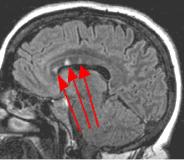

Fig. 4

Thin-section sagittal FLAIR images increase detection of small MS plaques even further, first reported by Hashemi, et al. (Ref. 1). They also have the advantage of clearly showing the corpus callosum and subependymal regions. An early sign of MS is subependymal nodularity and subcallosal striations (Ref. 1-2), not clearly visible on axial images. Fig. 3-4 in the same patient clearly show subcallosal MS plaques (arrows) along the undersurface of corpus callosum.